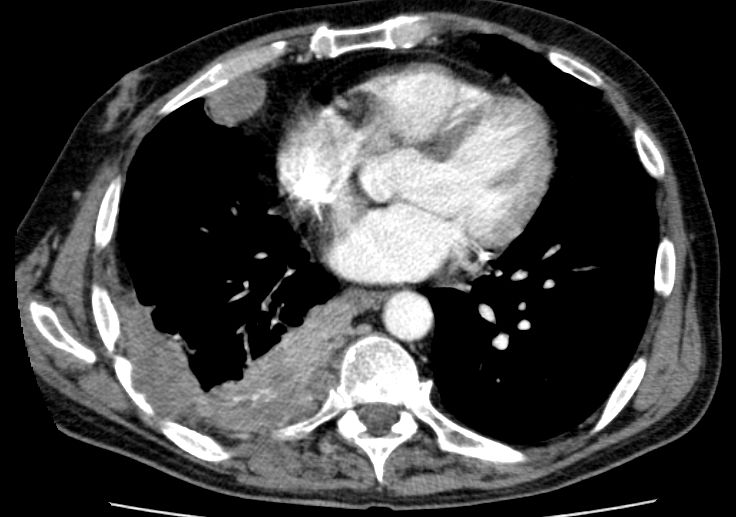

| BWS-Arrosion | BWK 12 - Arrosion bei Plattenepithelkarzinom des rechten Lungenunterlappens.![]() | |||

| Rippen-Arrosion | Pleurametastasen mit Rippen - Arrosion bei Plattenepithelkarzinom des rechten Lungenunterlappens.![]() |